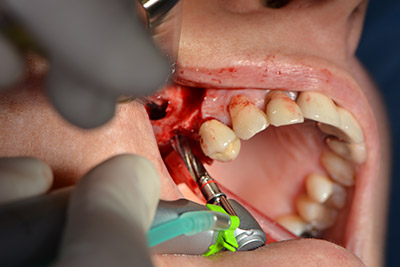

Следващата стъпка е синус лифт с непосредствено имплантиране. Implantmed е предварително настроен на първа позиция за букална фенестрация на стената на максиларния синус.

Фенестрацията е извършена при 35,000 rpm и след това носната лигавица е обработена по посока на челюстта (Фиг. 13 to 14).